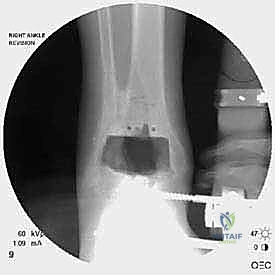

Step 2: Fracture Reduction and Plate Application

"Now, the reduction. Often, the fracture is at the apex of the lateral portion of the prosthesis, making standard lag-screw fixation challenging due to limited bone stock. We'll use a plate here. Assistant, gently reduce the fragments. I'll use a small reduction clamp to hold it. We need to restore the length and rotation of the fibula. Confirm reduction with fluoroscopy. See how it's aligned now? Good. Now, let's grab a small fragment plate, perhaps a 1/3 tubular plate or a specialized lateral malleolar plate. I'm going to pre-bend the plate to hook around the lateral malleolus tip. This contouring is crucial for proper fit and stability. We want it to sit flush against the bone."

TECH FIG 2 • Clinical photograph reveals contouring of plate ( E ) and screw fixation above and below the fracture to maintain stability.

TECH FIG 2 • Intraoperative fluoroscopy demonstrates the fracture location ( C ) and reduction with plate fixation ( D ).

Step 3: Proximal and Distal Screw Fixation

"Once the plate is contoured and reduced, we'll apply it proximally to the fracture first. We need at least three screws traversing the syndesmosis, if possible, to anchor the plate securely to the tibia. These will be cortical screws. Drill, measure, tap, and insert. Ensure these screws are not impinging on the anterior aspect of the tibia or the deep peroneal nerve.

For distal screw fixation, we generally have room for two screws. The first, more proximal screw, should be placed with lag technique if feasible, to achieve interfragmentary compression across the fracture line. This is critical for primary bone healing. The second screw is placed intramedullary, at the very tip of the lateral malleolus, to provide additional stabilization and prevent rotational instability of the distal fragment. Sometimes, a long screw can pass through the plate, into the distal fragment, and then into the medullary canal of the fibula. Again, fluoroscopy is essential to guide every step, ensuring proper screw length and avoiding joint penetration. Let's get a final fluoroscopic view in AP, lateral, and mortise to confirm excellent reduction and hardware placement."